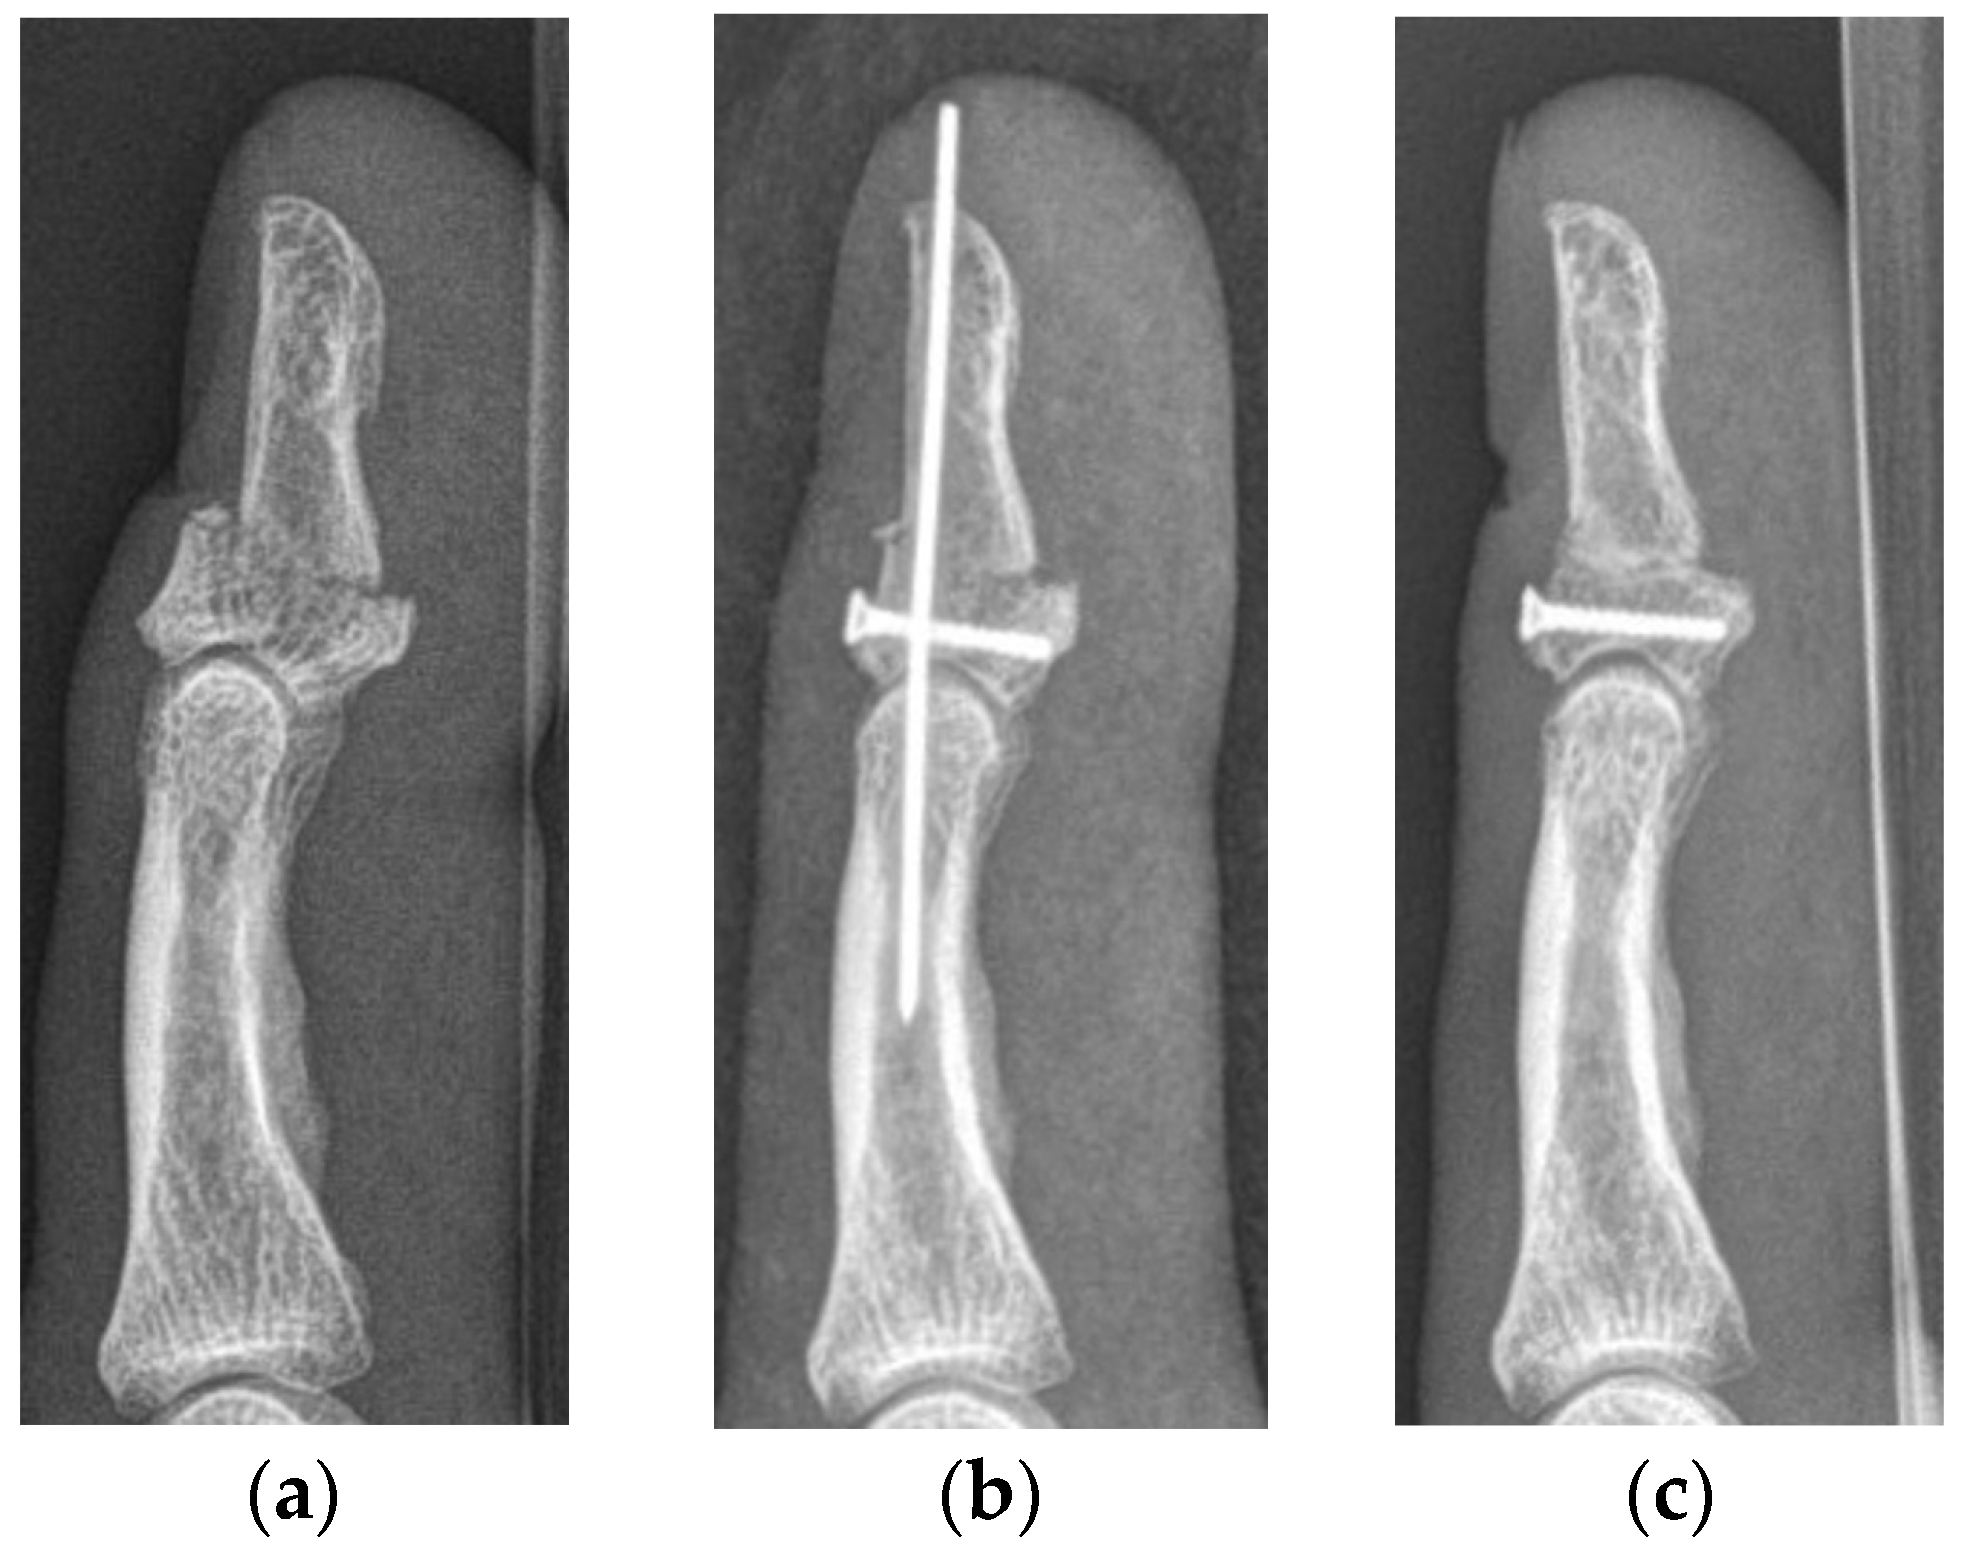

Figure 3. Lateral radiographs of a type Va jersey finger, with significant retraction of the FDP tendon together with a bony avulsion fragment (a). The same patient after surgical refixation using a K-wire and a Bunnell pull-out suture as proposed by Al-Quattan et al. [6] (b). Lateral radiographs after implant removal 6 weeks after surgery (c). The functional outcome of this patient was classified as fair.

The median primary bony displacement in patients in the SD subgroup was 0.9 mm (0.6–3.0 mm). Significant retraction (level of PIP joint) of the FDP tendon was observed in every patient. The functional outcome in cases who subsequently underwent surgery was poor in one patient and fair in another. One patient who presented at our department was in clinical care at another trauma center. He had already undergone surgery; however, he showed signs of pseudarthrosis when he presented at our clinic and had already received an appointment for revision surgery. He consulted our department only once; further patient history and functional outcome were not recorded. Surgery was performed using Bunnell pull-out sutures and K-wires in all patients (Figure 3).

In the case series of Al-Quattan [6], who was the first to describe jersey finger type V, all operated cases reached an almost unimpaired ROM after treatment without concomitant complications. The reconstruction of type Va was performed using only one 3–0 polypropylene pull-out suture; in cases of type Vb injuries, K-wires for DIP joint stabilization were added. Although we used the same technique for reconstruction in some patients, the achieved results were not as favorable. We also encountered one case with postoperative nail deformity, as this is a common complication when using pull-out sutures for reconstruction. The patient receiving reconstruction with three K-wires showed a worse radiological outcome, resulting in joint stiffness after a postoperative period of 4 months. Although this method of refixation showed sufficient results in the treatment of jersey finger type III injuries [17], it seems inappropriate for jersey finger type V injuries. Another fateful outcome was observed in the type Vb injury reconstructed with a Bunnell pull-out suture and one K-wire, resulting in severe osteoarthritis after 6 months. Refixations with these techniques seem to treat these severe injuries insufficiently.